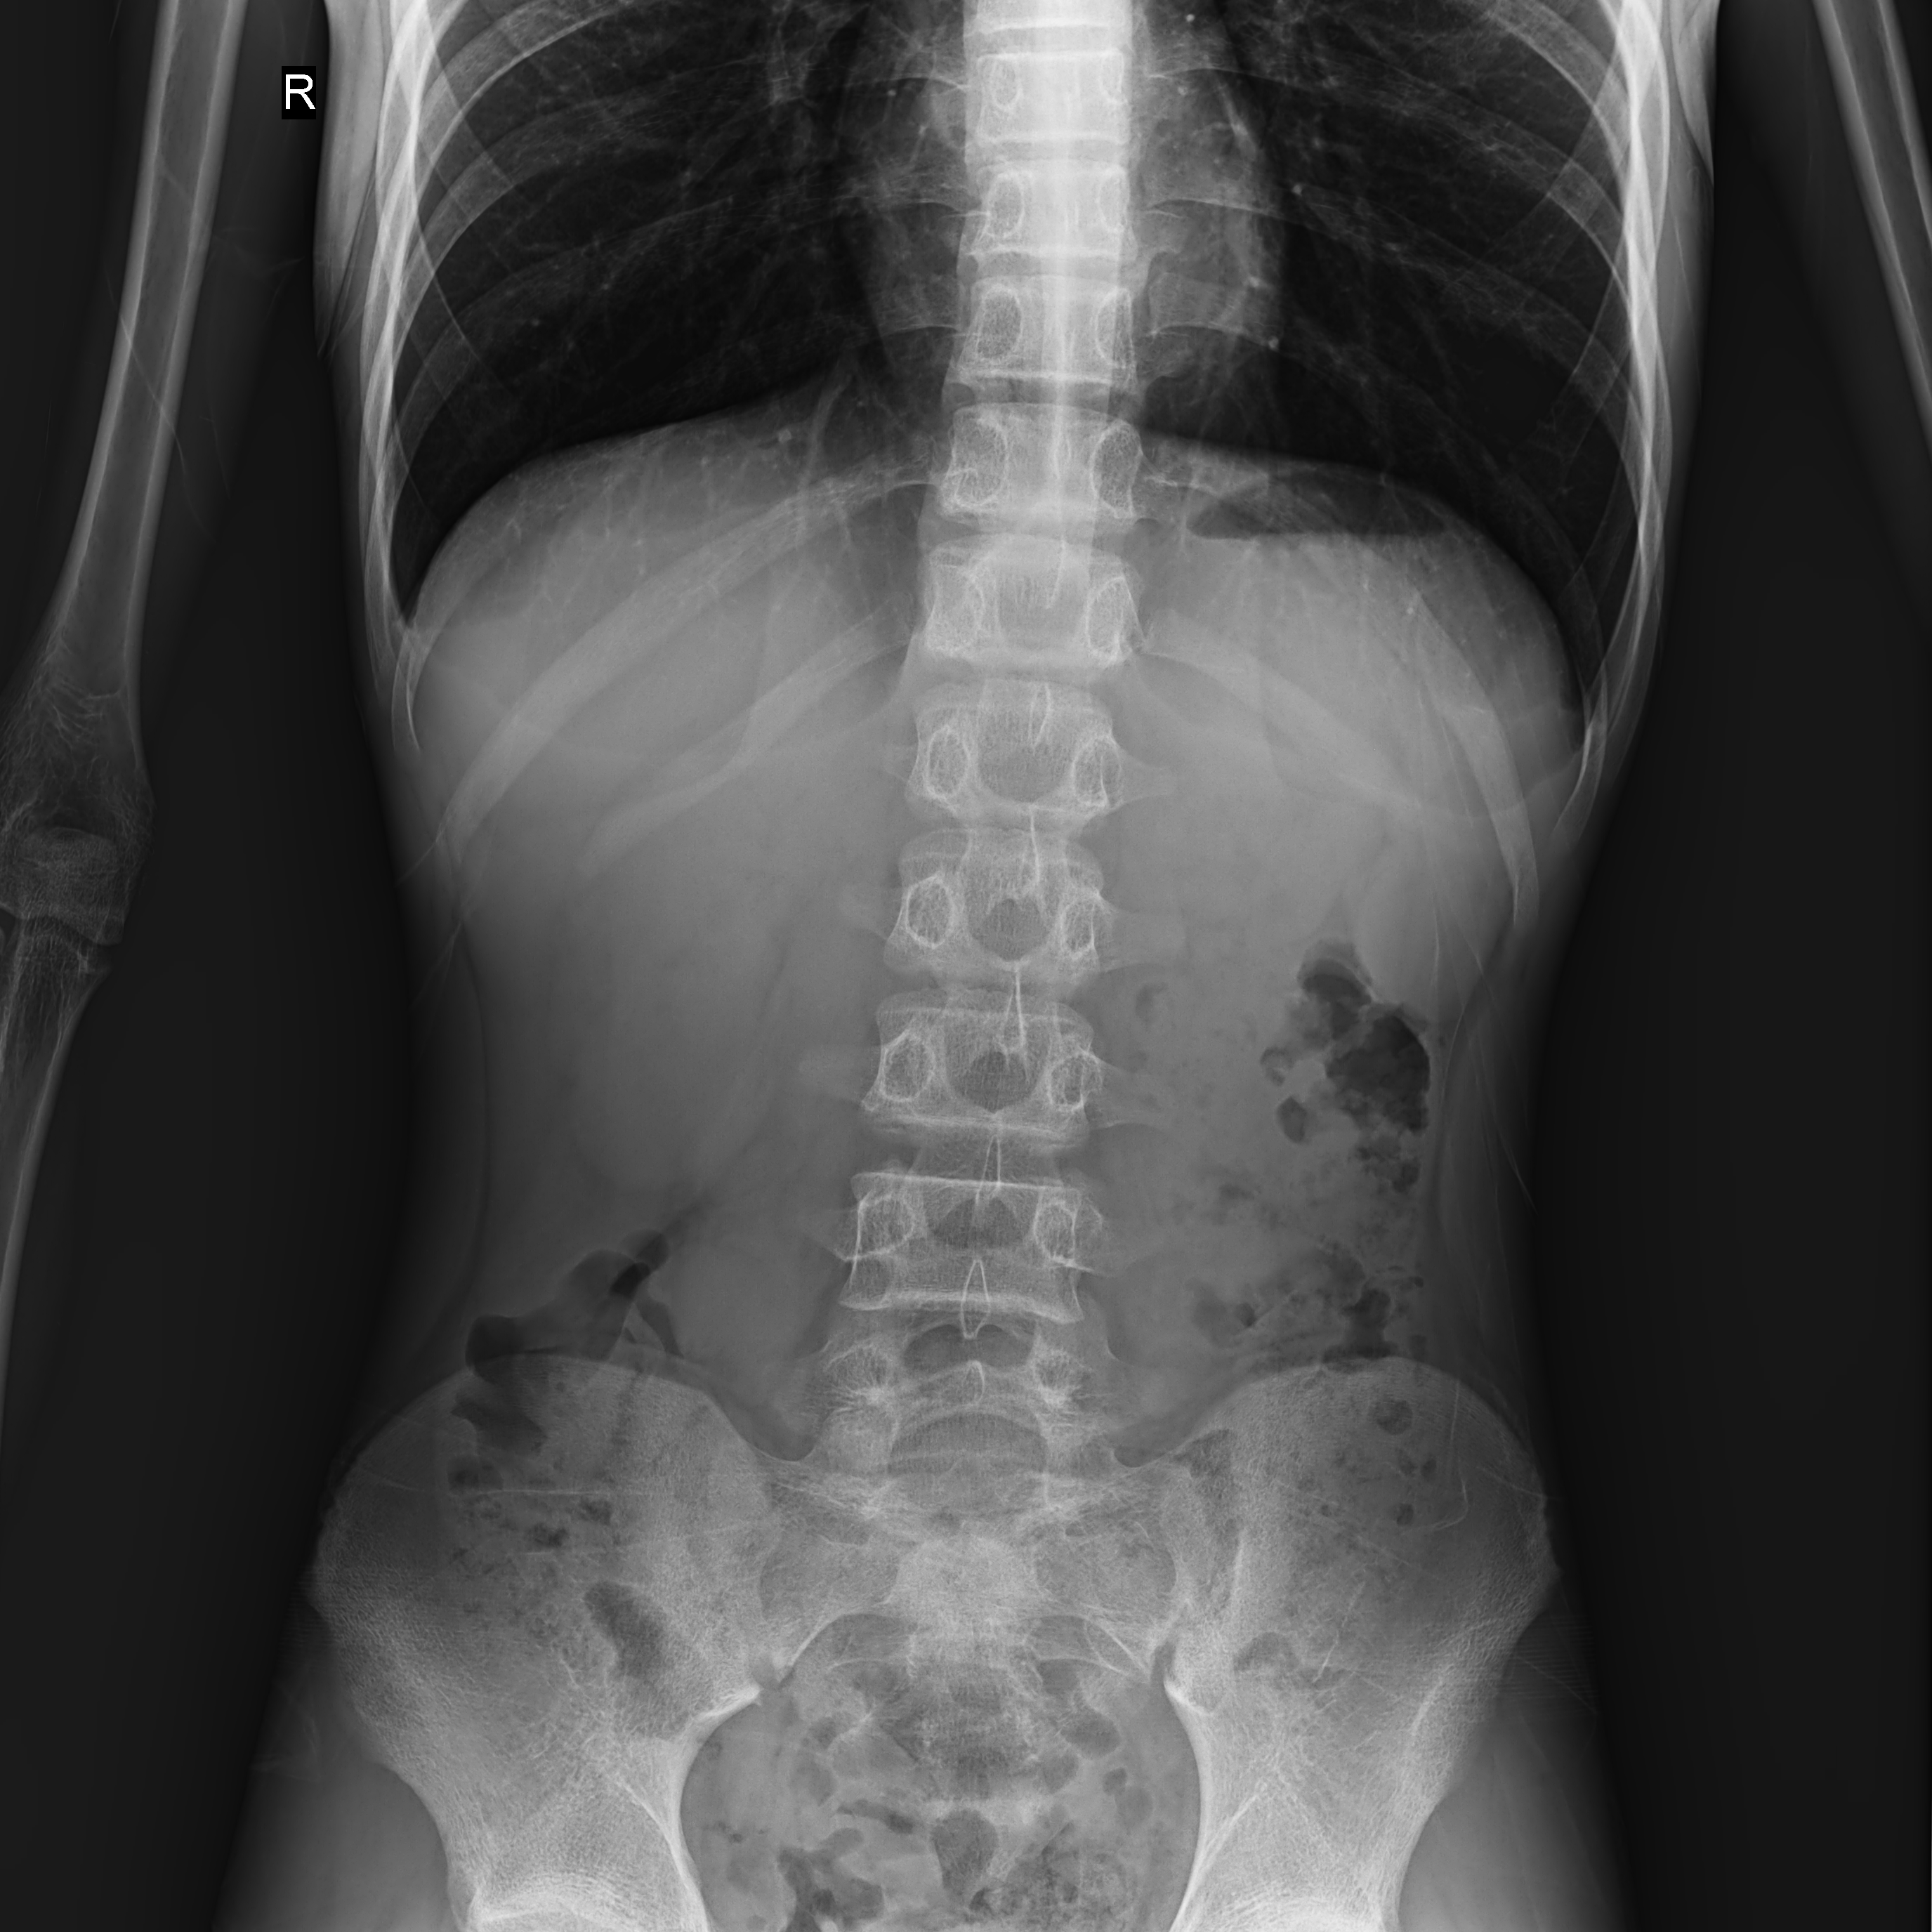

普利德醫(yī)療自主研發(fā)的新一代數(shù)字化X線透視攝影系統(tǒng),可應(yīng)用于DR攝影、數(shù)字透視、數(shù)字造影以及可視化精準(zhǔn)DR拍片等多種臨床X線檢查領(lǐng)域。

● 17*17英寸的超高清像素動(dòng)態(tài)平板探測(cè)器,更大的視野范圍,無(wú)需移動(dòng)即可觀察整個(gè)動(dòng)態(tài)過(guò)程,避免拖尾、噪聲對(duì)圖像的影響;

● 高效動(dòng)態(tài)平板技術(shù),圖像不會(huì)有幾何畸變,提供高分辨率和精確的圖像,為醫(yī)生臨床診斷提供精準(zhǔn)依據(jù);

點(diǎn)片裝置移動(dòng)范圍大,無(wú)需患者移動(dòng)就能完成全身各部位的檢查;

床面橫向移動(dòng),輕松實(shí)現(xiàn)機(jī)動(dòng)人不動(dòng)。